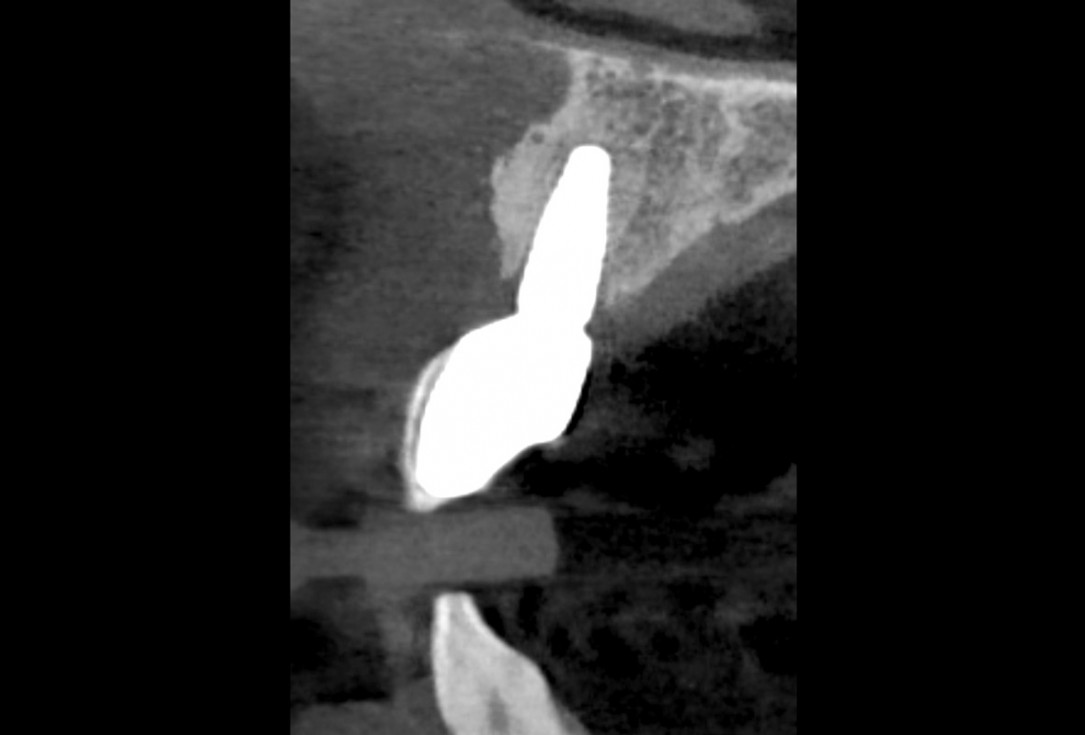

34/35 - 5 y post op CBCT - Coronal view showing the upper left central incisor implantBlock grafting in the aesthetic zone with maxgraft®, Jason® membrane and cerabone® - Dres. H. Maghaireh and V. Ivancheva

35/35 - 5 y post OP CBCT -Sagittal viewBlock grafting in the aesthetic zone with maxgraft®, Jason® membrane and cerabone® - Dres. H. Maghaireh and V. Ivancheva